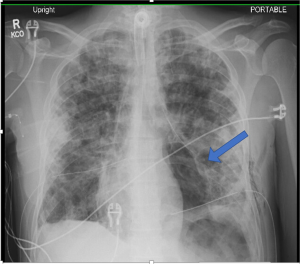

A 32-year-old male with a history of IV drug and tobacco use presented to the Emergency department with blunt chest trauma. He had pre-existing pulmonary septic emboli and developed severe acute respiratory distress syndrome (ARDS) requiring intubation and veno-venous extracorporeal membrane oxygenation (ECMO). While on ECMO he developed bilateral pneumothoraces from ruptured blebs complicated by bilateral bronchopleural fistulae. CT scan was obtained that revealed small volume pneumopericardium as well as bilateral pneumothoraces (Figure 1). Corresponding chest X-ray is seen in Figure 2. Several days after ECMO decannulation the patient developed acute agitation and hemodynamic instability. A chest X-ray was obtained that revealed air in the pericardial sac, cardiac compression, and mediastinal shift consistent with tension pneumopericardium (Figure 3). He was taken emergently to the operating room for pericardial window and drain placement. He was returned to the surgical ICU in critical, but improved, condition. Though rare, tension pneumopericardium should be on the differential diagnosis for shock in patients with blunt chest trauma, emphysematous lung disease, or bronchopleural fistula.